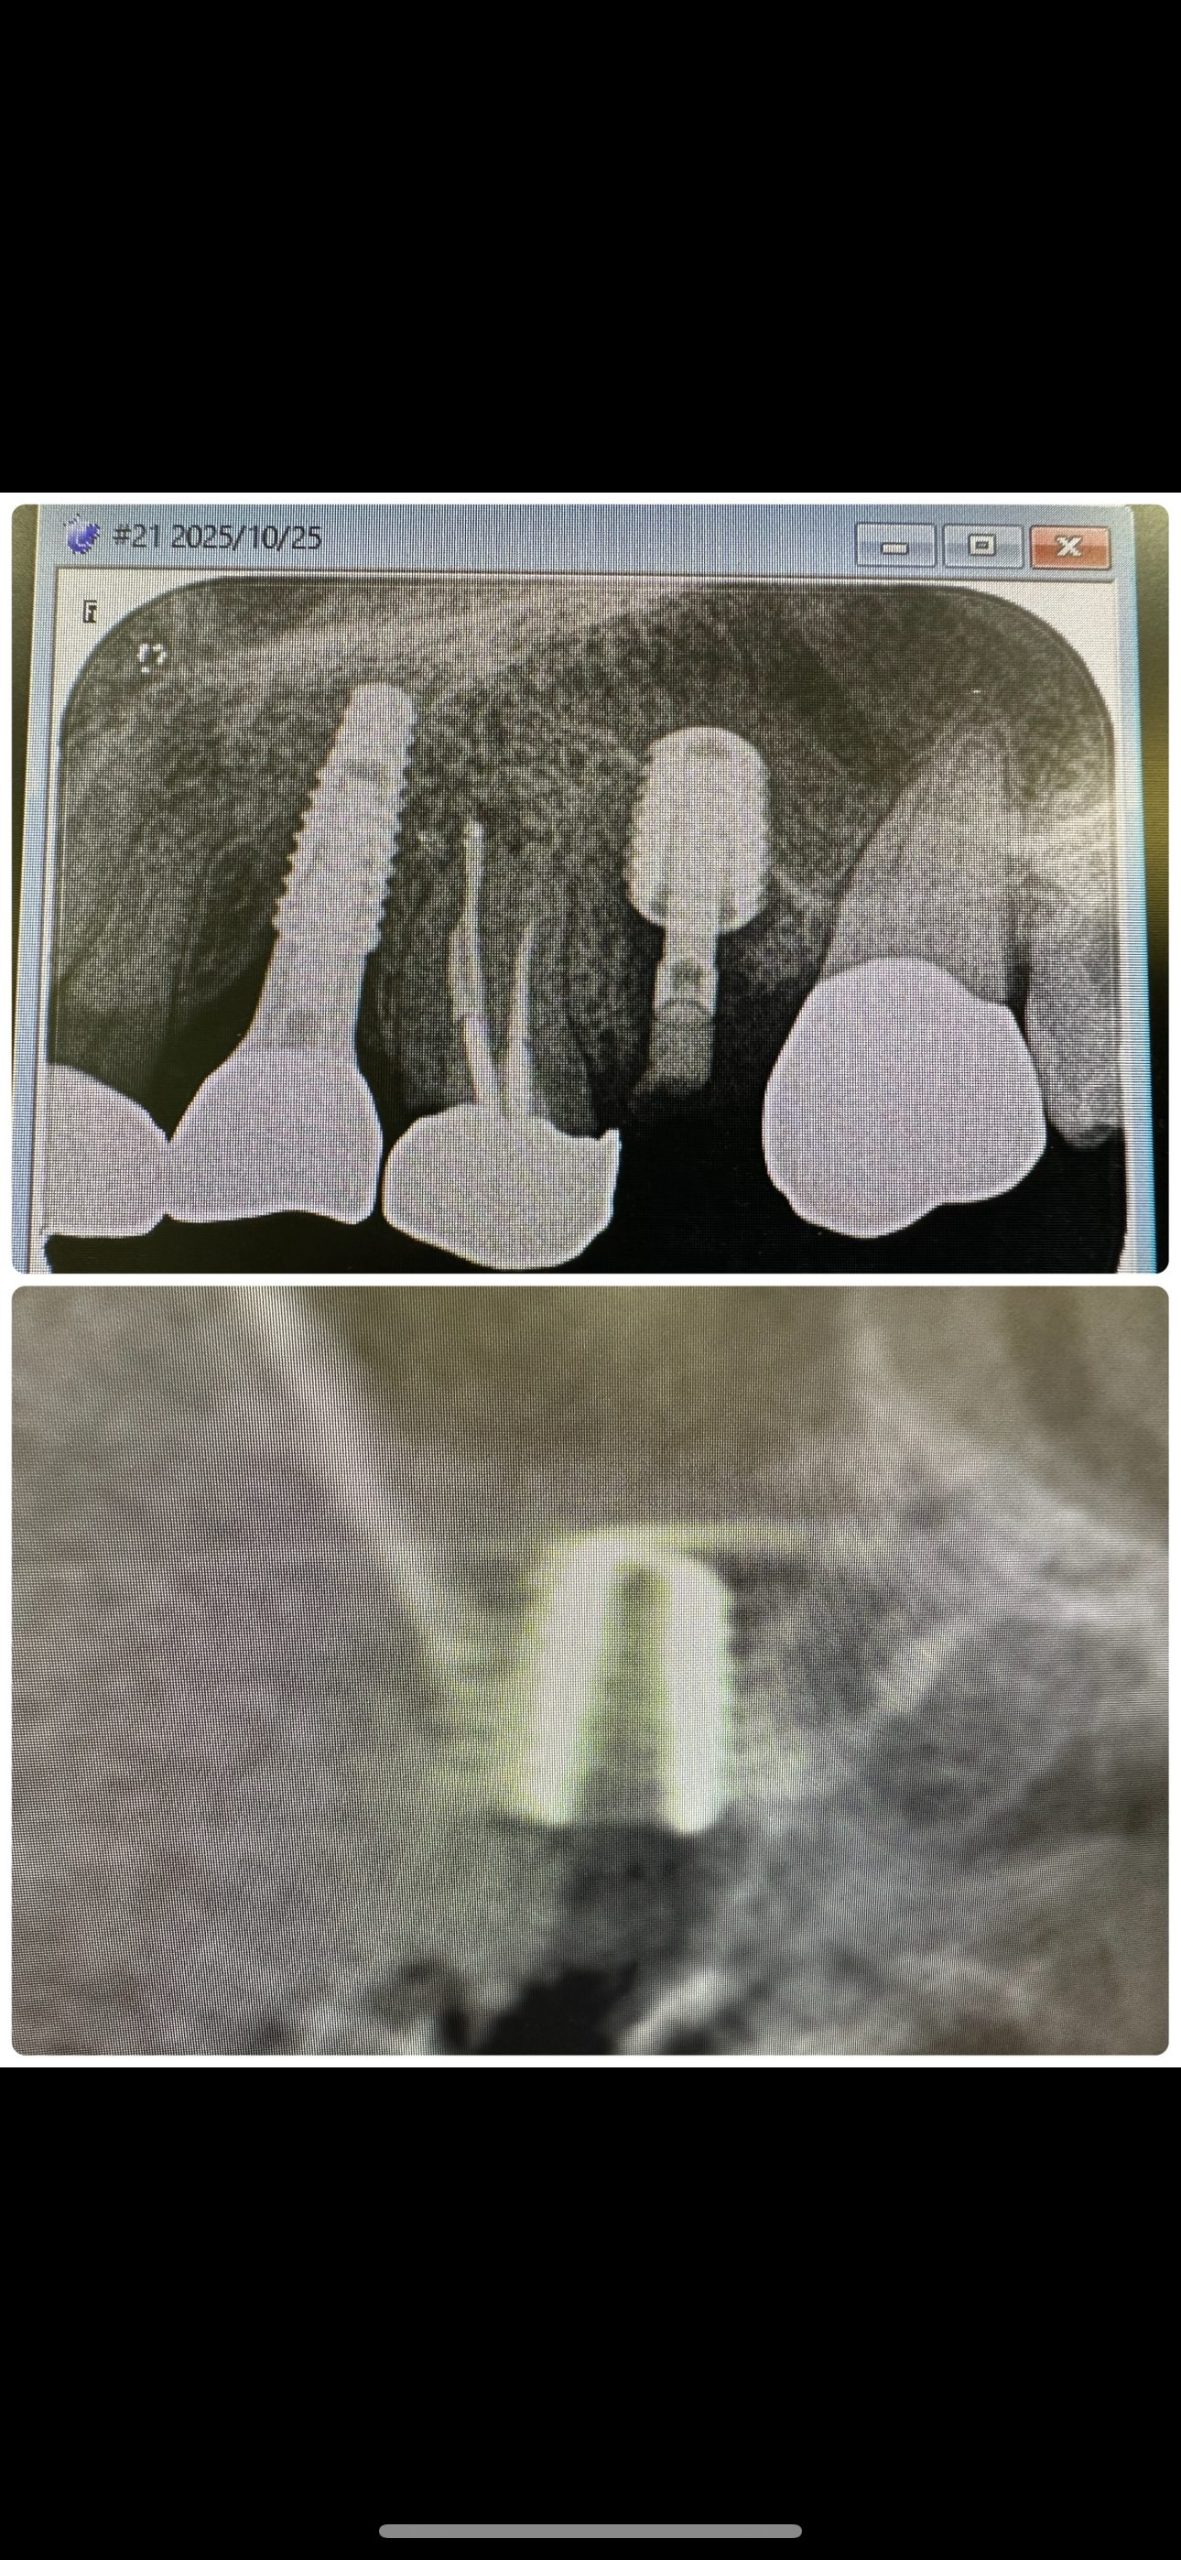

昼からインプラントオペ、ソケットリフト併用

切開から埋入まで20分で終わり💪

毎度同じようなリフト🤪

デンサーリフトは早い、安全!